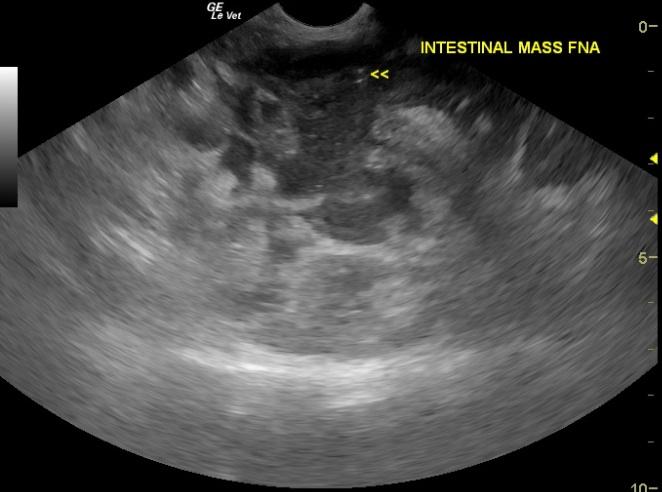

A 12-year-old MN DSH cat was presented for acting hungry but not eating, polyuria, and progressive weight loss. The only significant abnormality on physical examination was a thickened intestine.